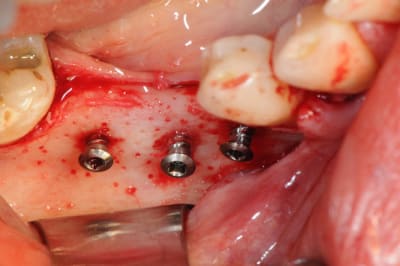

Clio, joli boulot, d'accord avec toi pour l'allogène mais je ferai la même remarque qu'à D57. un positionnement plus adéquat des vis et un protocole plus précis etc.. te permettrait d'éviter d'avoir en face de la vis mésiale une résorbtion osseuse. Du coup ton implant mésial n'a pas beaucoup d'épaisseur d'os en vestibulaire.

Comme le signale Joseph,l'implant mésial n'a effectivement pas beaucoup d'épaisseur d'os en vestibulaire.

désolé pour la qualité des photos, mais on voit quand même le volume osseux vestibulaire, qui a mon sens est suffisant.

photo 6-7-8 : retrait des vis FAST ayant servi de piquet de tente à la ROG

Sur la photo vis en place : elle est déjà un peu dévissée, ou il y a eu 2 mm de perte du matériaux ? ( c'est ce que j'ai eu aussi les deux fois ou j'ai fait cette technique ).

En effet si on compare la photo de ton post initial par rapport à la photo de la réouverture, on peut voir que la vis dépasse toujours autant par rapport au niveau osseux initial.

pour clio et jeff, la photo montrant la vis est trompeuse et je comprends mieux vos réactions.

en fait elle n'était pas dans sa position initiale car j'ai fait la photo avec la vis ayant été retirée à moitié.

photos 1 et 2 mise en place des vis et comblement osseux.

photo 3 et 4 le niveau osseux n'a pratiquement pas bougé.